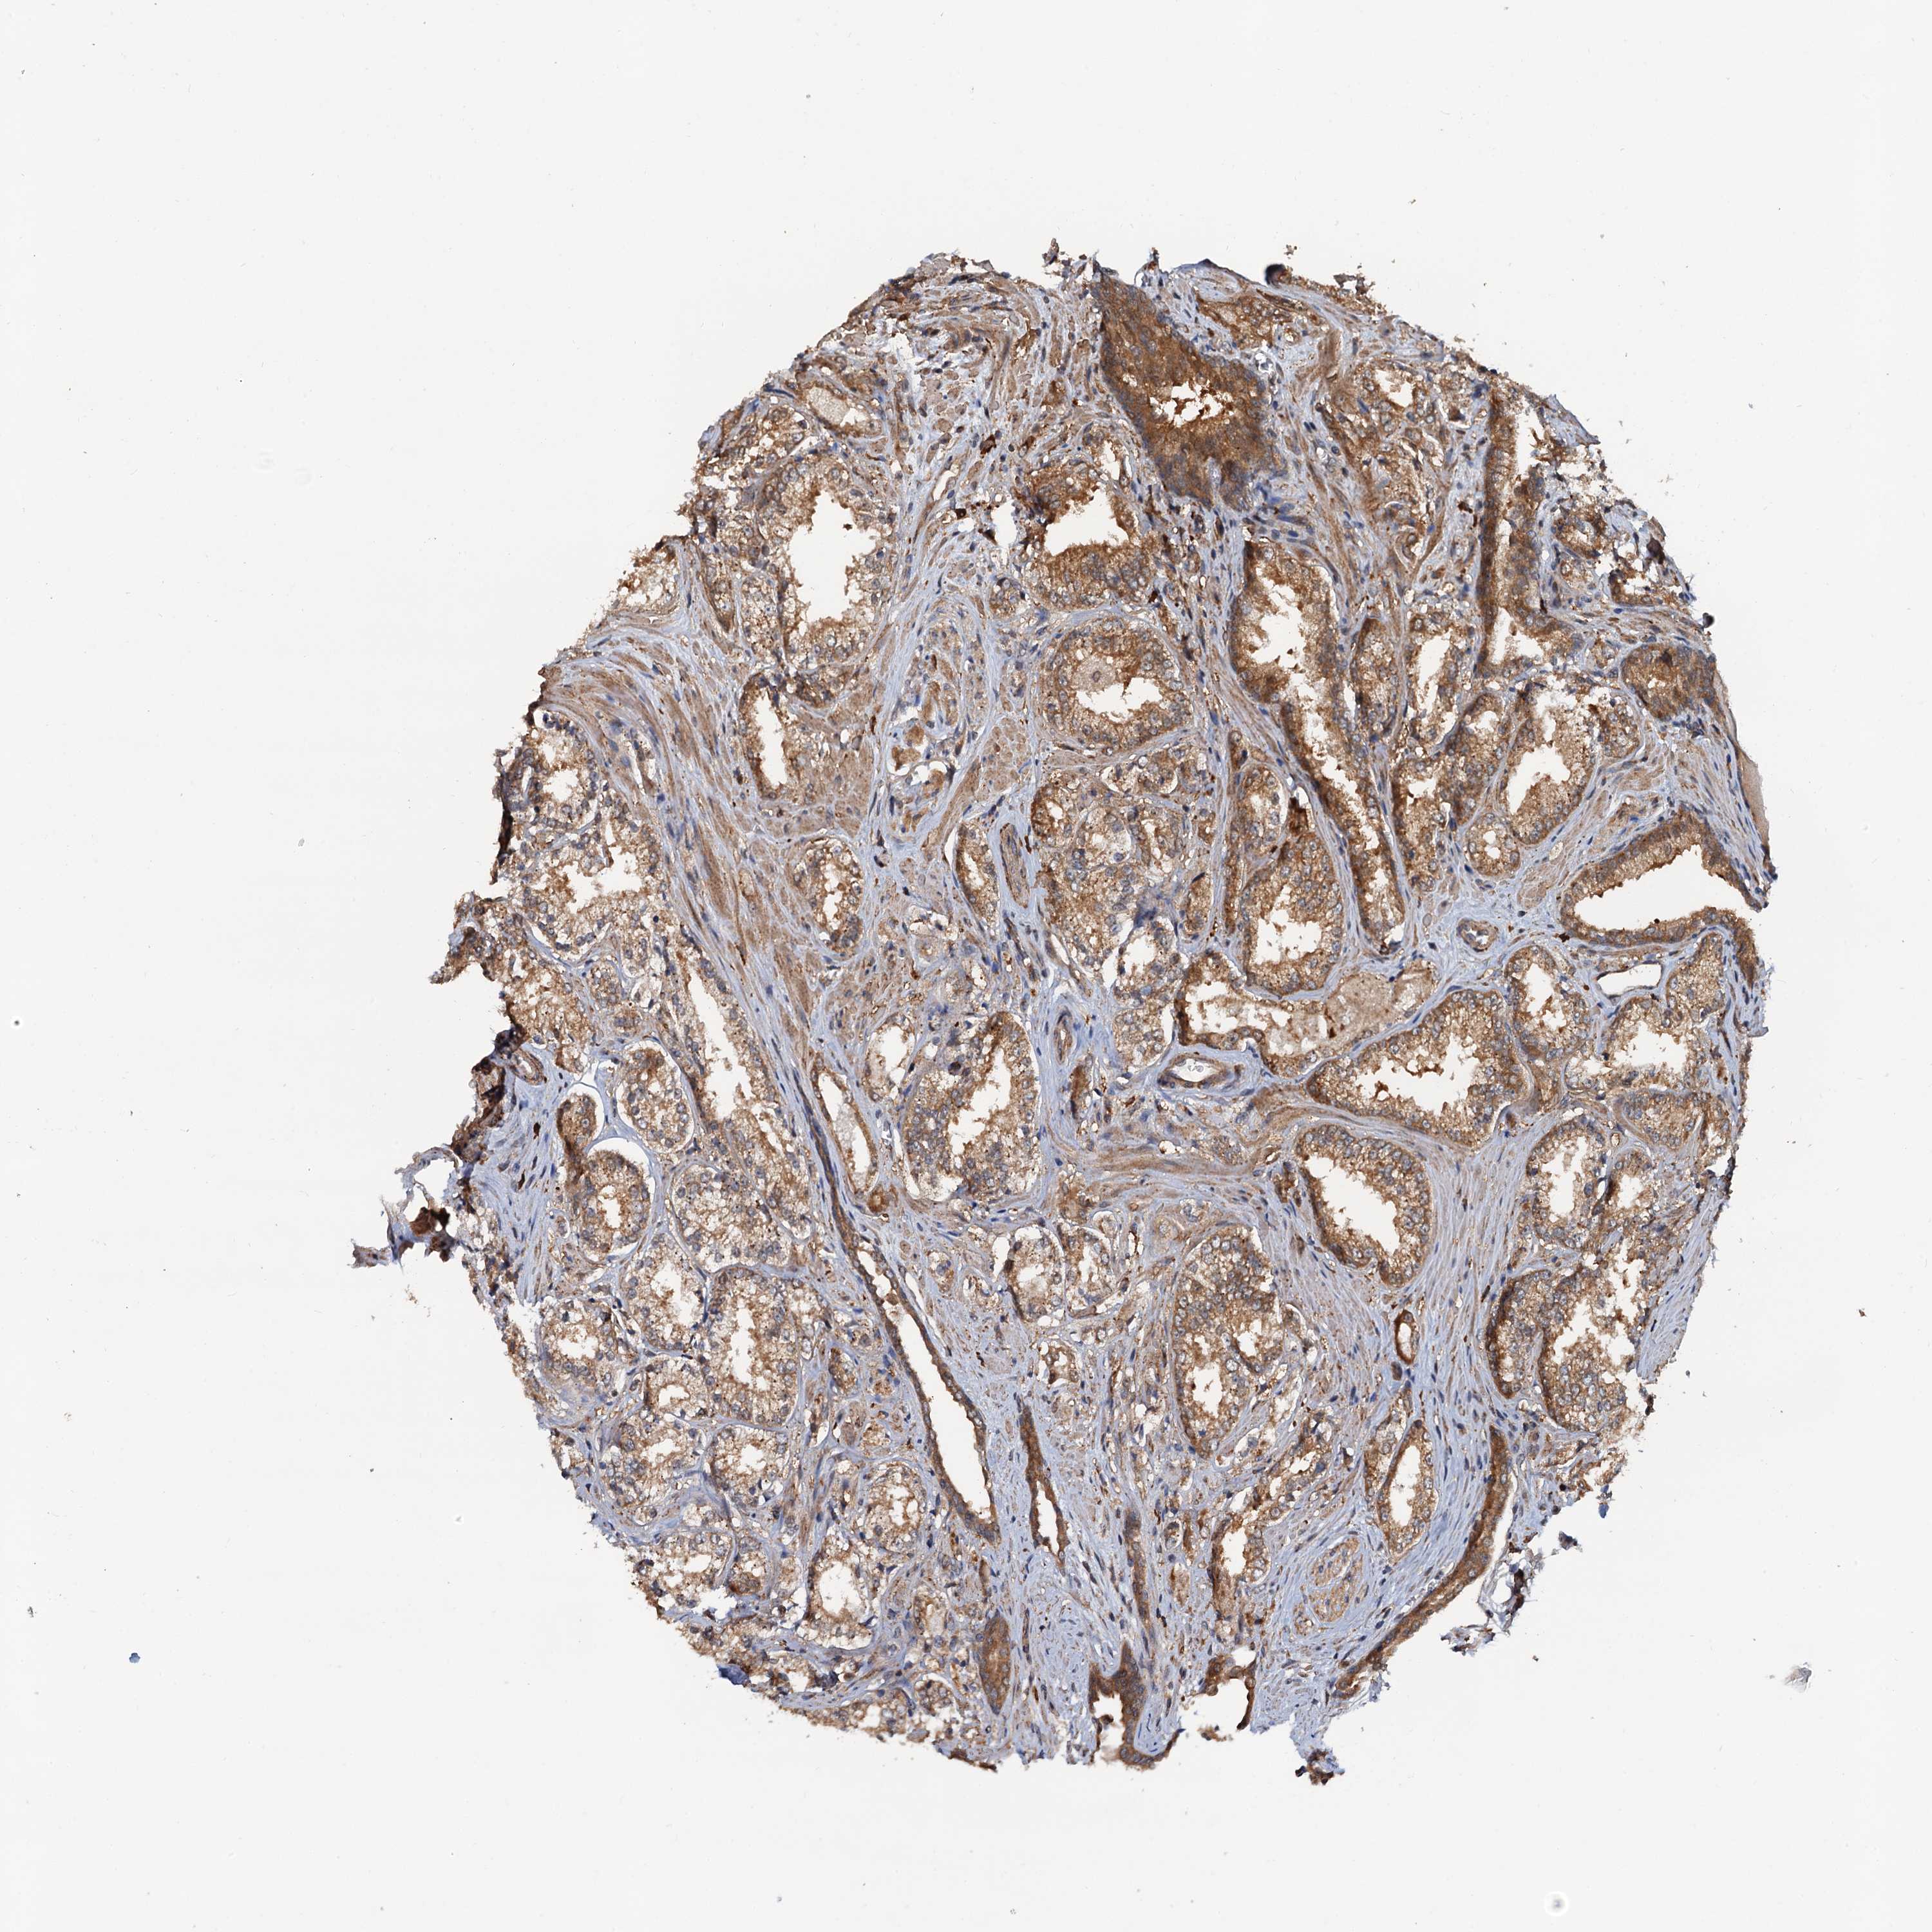

PROSTATE CANCER - Protein expressioni

A mouse-over function shows sample information and annotation data. Click on an image to view it in a full screen mode. Samples can be filtered based on level of antibody staining by selecting one or several of the following categories: high, medium, low and not detected. The assay and annotation is described here.

Note that samples used for immunohistochemistry by the Human Protein Atlas do not correspond to samples in the TCGA dataset.

Antibody stainingi

Antibody staining in the annotated cell types in the current human tissue is reported as not detected, low, medium, or high, based on conventional immunohistochemistry profiling in selected tissues. This score is based on the combination of the staining intensity and fraction of stained cells.

Each image is clickable and will lead to virtual microscopy that enables deeper exploration of all samples and also displays staining intensity scores, fraction scores and subcellular localization as well as patient and tissue information for each sample.

Antibody HPA039371

Antibody HPA040174

Staining

High

Medium

Low

Not detected

Intensity

Strong

Moderate

Weak

Negative

Quantity

>75%

75%-25%

<25%

None

Location

Nuclear

Cytoplasmic/membranous

Cytoplasmic/membranous,nuclear

Adenocarcinoma, NOS

Adenocarcinoma, High grade

Adenocarcinoma, Low grade